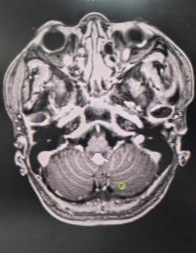

此次帮扶的核心技术提升,是刘定阳亲自现场指导并开展4台神经外科四级高难度手术,为我院功能神经外科发展提供了有力技术支撑。其中三叉神经微血管减压术作为三叉神经痛外科治疗的重要术式,在刘定阳现场带教与指导下顺利实施,为科室开展相关手术积累了关键经验。

同期,还顺利完成Chiari畸形后颅窝切开减压术、幕下深部延髓旁占位性病变切除术、左侧顶叶脑内占位病变切除术,进一步完善了我院复杂颅脑疾病手术体系,为今后我院功能神经外科的持续发展提供了有力保障。